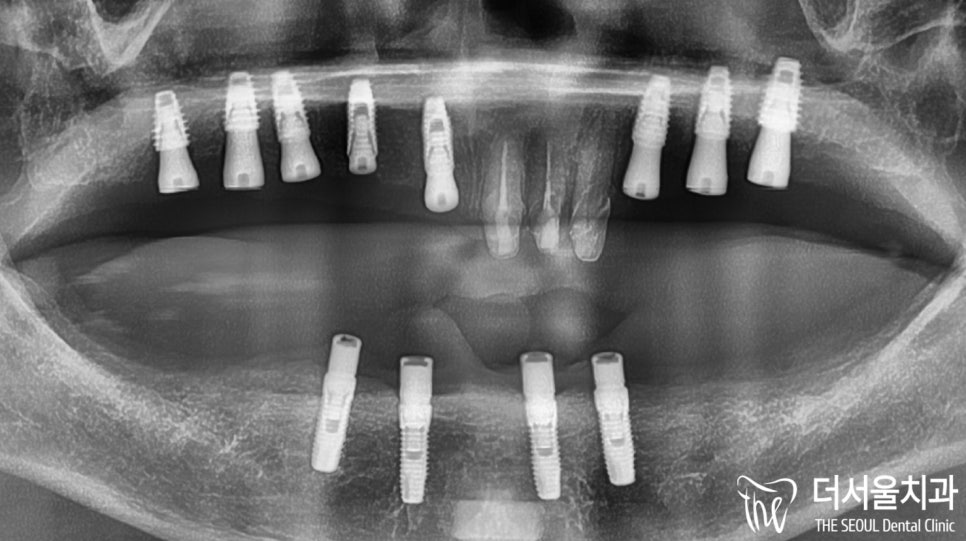

사진을 보면 잇몸뼈가 거의 없습니다.

자세히 보면 움푹 패어있어

뼈이식을 피할 수 없었는데요.

엑스레이로 잇몸에 남아있는 뼈를 체크한 결과,

그렇게 좋은 상태는 아니었습니다.

산성역치과 에서 확인한 결과,

전반적으로 골폭이 좁은 상태였습니다.